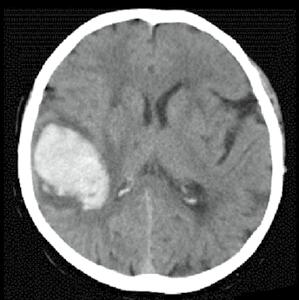

Kazuistika

Osmdesátiletá pacientka, z kardiologických důvodů dlouhodobě na warfarinu, hypertonička. Náhlé bezvědomí, pád z postele. Při přijetí somnolentní, jednoduchým výzvám vyhoví, hlavu a bulby stáčí doprava, levostrannými končetinami hůře pohybuje. Zemřela 5. den po mozkové příhodě.

Obr. A2.1–A2.4 Intracerebrální krvácení v akutním stadiu (1. den), oxyhemoglobin, ale již příměs deoxyhemoglobinu